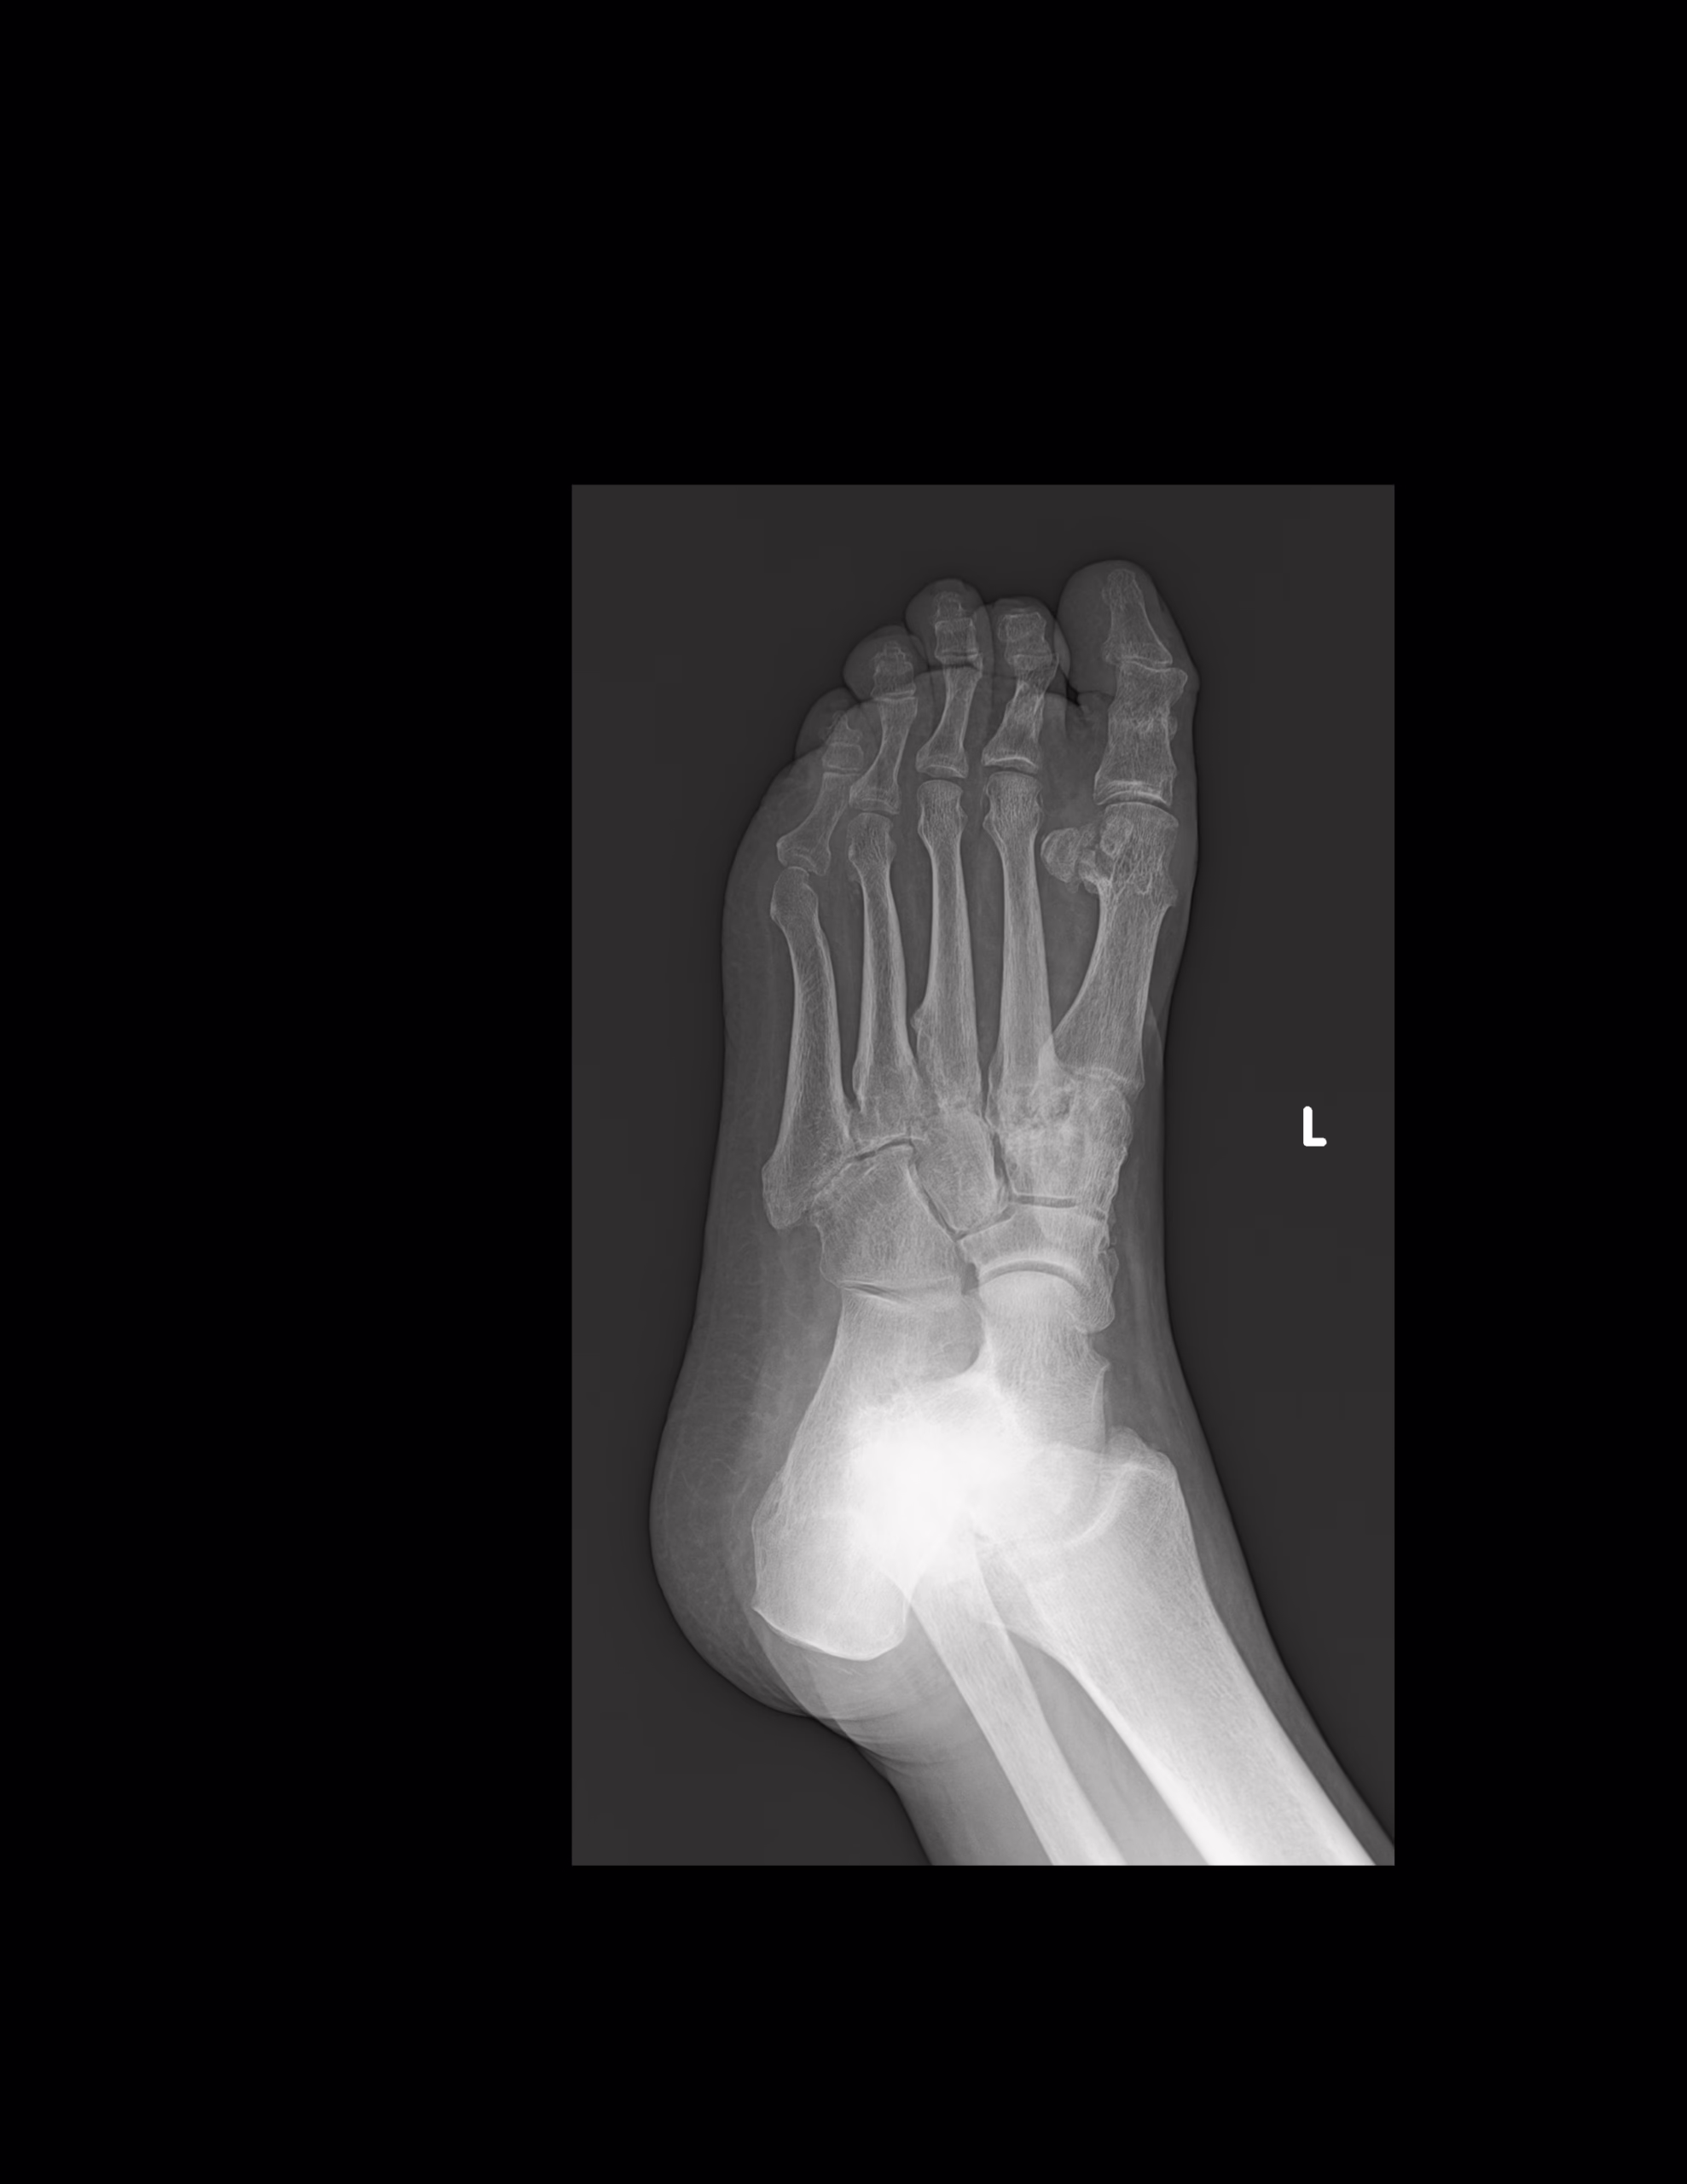

RADIOGRAFIA AP Y OBLICUA DE PIE

LAS PROYECCIONES RADIOLOGICAS OBTENIDAS NOS MUESTRAN LOS SIGUIENTES HALLAZGOS

-Se observa trayecto compuesto a nivel de proceso posterior del astrágalo. 2do cuneiforme con trazo longitudinal no desplazada. A nivel de base de 2do metatarso, con aparente fractura. Existe espícula osteofítica en porción inferior de tuberosidad del calcáneo. Resto de huesos del tarso, metatarsos y falanges, con disminución de la densidad, sin evidencia de lesiones líticas, blásticas o perdidas de la contigüidad.

-Angulo metatarsofalángico del 1er ortejo de 22.6°

-Angulo intermetatarsiano de 13.2°.

EN EL PRESENTE ESTUDIO RADIOGRÁFICO, EXISTE APARENTE FRACTURA DEL PROCESO POSTERIOR DEL ASTRÁGALO. FRACTURA DEL 2DO CUNEIFORME CON ASOCIACIÓN DE APARENTE FRACTURA NIVEL DE BASES DEL 2DO METATARSIANO, CON EDEMA ASOCIADO.

EXISTE ESPOLÓN ÓSEO DEL CALCÁNEO.

HALLUX VALGUS MODERADO.